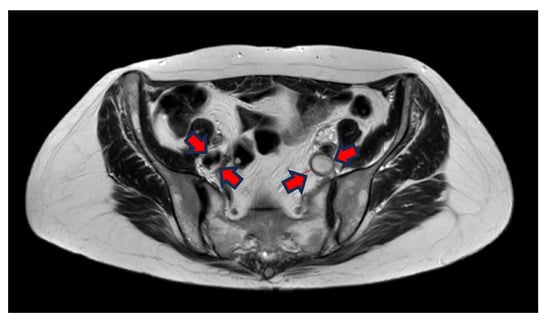

The liquid blood in veins and arteries appears white, whereas solidified blood, as in vein thrombi, is dark, spanning from grey to black (Figure 1A,B).

The T2w sequence is less sensitive to artefacts than the BFFE, which can be extremely important for patients having more DVT or being treated with stents earlier. The T2w has a better linear resolution and gives better tissue differentiation in the images (see differences between Figure 1 and Figure 2).

A total of 123 patients received both MRV and DSP, resulting in 246 image sets to be analysed by two observers, both experienced in interventional radiology in peripheral vascular disease between 10 and 27 years of experience, respectively. In total, 496 segments were analysed for occlusion, stenosis (partial thrombosis), or patent vein (no thrombosis) at seven different anatomical landmarks cf. Figure 1.

Figure 1. (A) Coronal BFFE shows a hypointense signal and a bit ecstatic thrombosed left external iliac vein. The right iliac vein has a hyperintense signal and is patent. (B) Transversal BFFE shows ecstatic and thrombosed left iliac vein. The right iliac vein has a hyperintense signal and is patent.